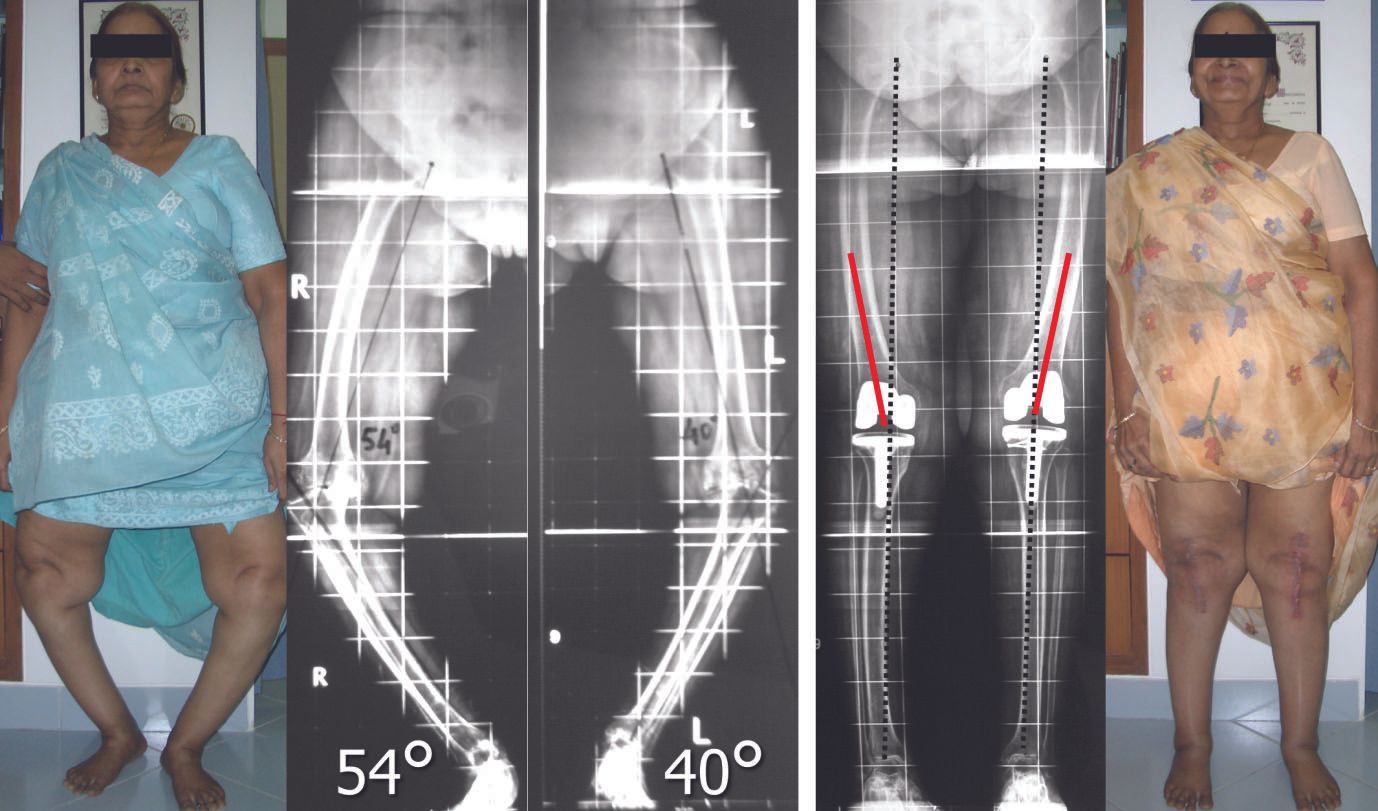

The accompanying articles address key areas in joint preservation and reconstruction. Lateral unicompartmental knee arthroplasty and medial unicompartmental knee arthroplasty are examined with respect to patient selection, procedural indications, and technical precision necessary to ensure durable outcomes. A dedicated contribution on hip arthroscopy on the orthopaedic table outlines technique optimization and complication avoidance. Finally, a pictorial and systematic approach to varus deformity provides a structured framework for deformity assessment and surgical planning.